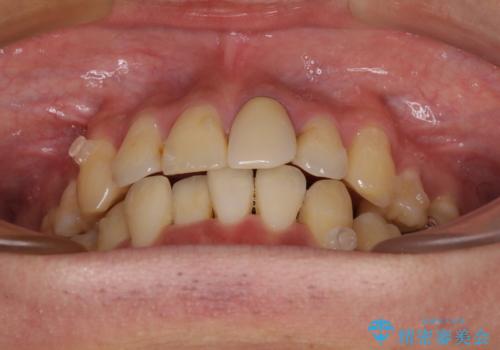

- 下顎の八重歯を気にして来院された患者様です。

左下以外、3本の第一小臼歯が既に抜去されており、左下は八重歯になっている状態でした。

左下の八重歯は手前に傾斜していたため、インビザラインによる抜歯矯正が可能と判断し、後方にある第一小臼歯を抜歯してインビザラインにて矯正治療を行うこととしました。

ワイヤー矯正と比較すると、八重歯が後方に傾斜した仕上がりとなりましたが、患者様ご希望のインビザラインにて十分な歯列を達成することができました。